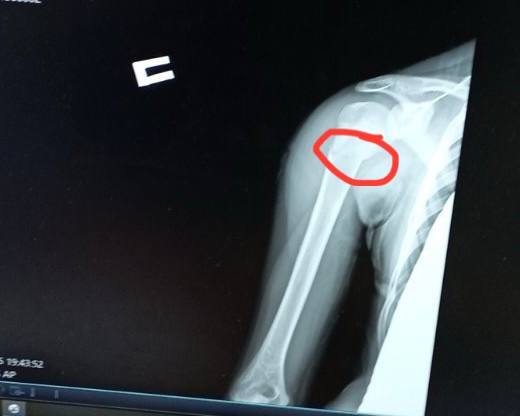

Ще одна пацієнтка відділення — 11-річна футболістка Юля, яка невдало впала на плече під час гри. Як наслідок — перелом плечової кістки зі зміщенням.

Раніше через такий перелом довелося б носити велику гіпсову пов’язку на руці — від кисті до плеча, також гіпс накладали б для фіксації і на обидва плеча. Після операції через 2-3 дні дівчинка вже вільно рухає рукою, не відчуває обмежень. На руці залишиться лише невеликий шрам 2-3 сантиметра. Через декілька тижнів дівчинка зможе повернутися до занять футболом.